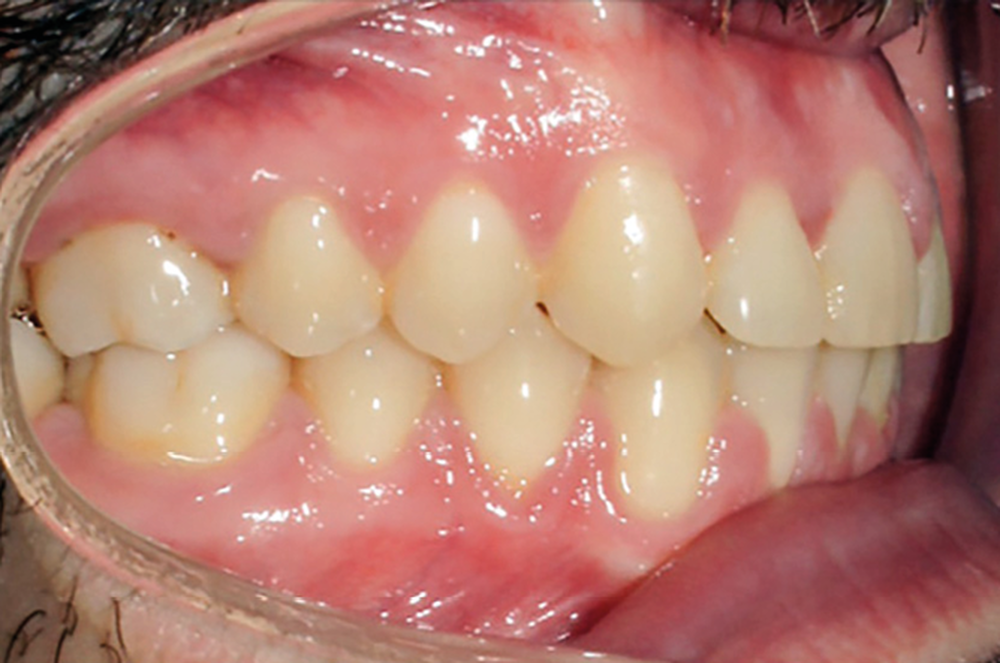

Examen endobuccal (fig. 2a-e)

L’arcade maxillaire est asymétrique, en hémi-lyre droite. Elle présente une mésio-position du secteur 1 en lien avec un encombrement antérieur estimé à 4 mm, se traduisant par une palato-position de la 12 et une rotation de la 11. On observe également des mésio-rotations des premières molaires et une palato-version incisive. L’arcade mandibulaire est ellipsoïde et présente un léger encombrement incisif (1 mm).

Concernant les relations occlusales, on observe une classe II complète subdivision droite. Le surplomb est absent et le recouvrement augmenté, estimé à 4 mm, a provoqué une usure des bords libres de 11 et 21 par attrition. Dans la dimension transversale, on constate une endoalvéolie maxillaire, ainsi qu’une concordance des médianes incisives entre elles, mais toutes deux déviées à droite par rapport au plan sagittal médian.